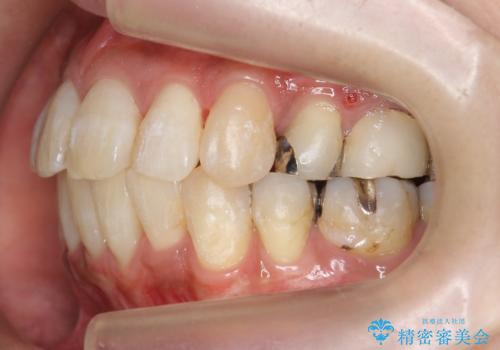

出っ歯 前歯のがたがた 口元を引っ込めたい

- 前歯のがたがた、出っ歯を主訴に来院。

がたつきは中等度で、上の前歯を下げるには歯を抜いてもスペースが不足していた為、上の奥歯を後ろに下げました。

下も混雑が激しく、歯を抜いてもスペースが不足していた為、下の前歯を少し削って小さくして並べています。

歯の移動量が大きく、また、少し歯も動きにくかったため矯正治療に時間はかかりましたがしっかり並べて前突感も大きく改善しました。

上の前歯が出ていた為、しっかり口を閉じることが難しい状態でしたが、楽に閉じられるようになりました。

側貌(横顔のライン)が治療前には下顎が後退したような状態が、口元を引っ込めたため相対的にしっかり前に出て見えるようになり、大きく改善しています。